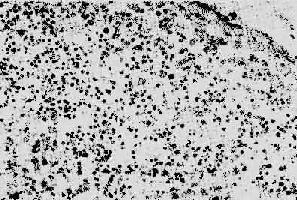

1. 淋巴样组织的变化早期及中期,淋巴结肿大。镜下,最初有淋巴滤泡明显增生,生发中心活跃,髓质出现较多浆细胞。随后滤泡的外套层淋巴细胞减少或消失,小血 管增生,并有纤维蛋白样物质或玻璃样物质沉积,生发中心被零落分割。副皮质区的淋巴细胞(CD4+细胞)进行性减少,代之以浆细胞浸润。晚期的淋巴结病 变,往往尸检时才能看到,呈现一片荒芜,淋巴细胞,包括T、B细胞几乎均消失殆尽,无淋巴滤泡及副皮质区之分,仅有一些巨噬细胞和浆细胞残留(图 4-15)。有时特殊染色可显现大量分枝杆菌、真菌等病原微生物,却很少见到肉芽肿形成等细胞免疫反应性病变。

图4-15 AIDS淋巴结

淋巴细胞明显减少,无淋巴滤泡及副皮质区之分